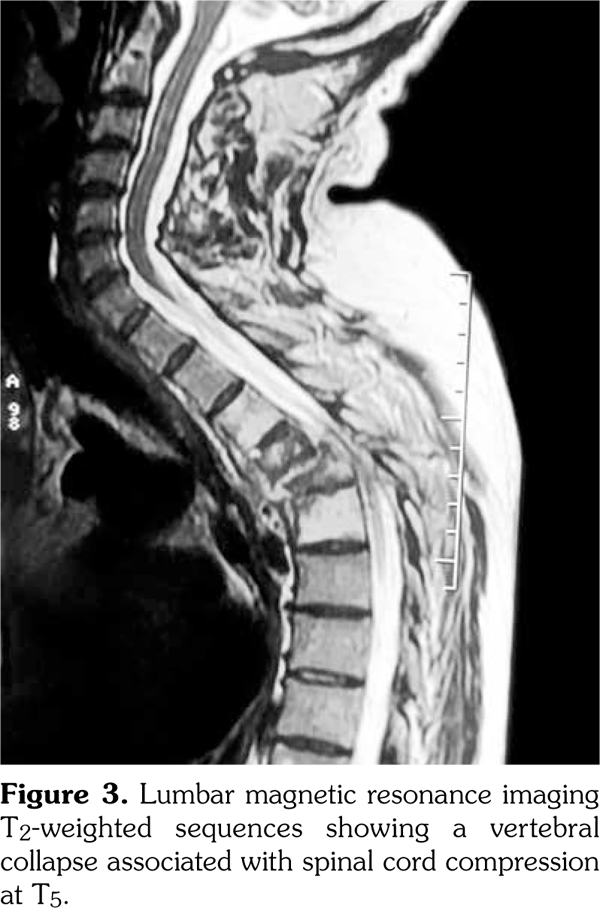

Thus, the diagnosis of SAPHO syndrome was established. Despite the use of nonsteroidal antiinflammatory drug, the disease remained active as attested by Bath Ankylosing Spondylitis Disease Activity Index at 6.7 at three-month follow-up. Then, the patient was lost to follow-up. One year later, he presented with hypesthesia and muscle weakness of his lower limb associated with kyphotic deformity and sphincter symptoms. He was unable to walk. Magnetic resonance imaging showed a vertebral collapse associated with spinal cord compression at T5 (Figure 3). Surgical treatment based on decompression and reconstruction with screw fixation was performed (Figure 4). The histopathology of the specimen obtained surgically showed nonspecific osteomyelitis with an infiltration of inflammatory cells and abnormal fibrous hypertrophy among the trabecular bone. One year later, etanercept was administered at a dose of 50mg weekly, leading to complete resolution of articular manifestations. Clinical remission was obtained under etanercept (Bath Ankylosing Spondylitis Disease Activity Index at 2.1). After two years of follow-up, patient’s paralysis improved by surgery, and he was progressively able to walk.

The spinal lesions in SAPHO syndrome usually have a good prognosis and rarely cause neurological deterioration.(5) In fact, they generally have an insidious onset and repeated recurrence and remission. In SAPHO syndrome, destructive lesions progress associated with marginal sclerosis explaining why destructive spondylodiscitis progresses slowly. However, if the speed of destruction by inflammation is faster than that of sclerotic reaction, the spinal structure would break.(8) We described herein a case of SAPHO syndrome complicated by severe destruction and kyphotic deformity leading to paralysis. To our knowledge, there are only seven cases of SAPHO syndrome with neurological deficit summarized in Table 1.(9-14) Surgery was performed leading to improved neurological signs.